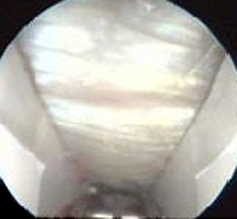

Endoscopic CTR